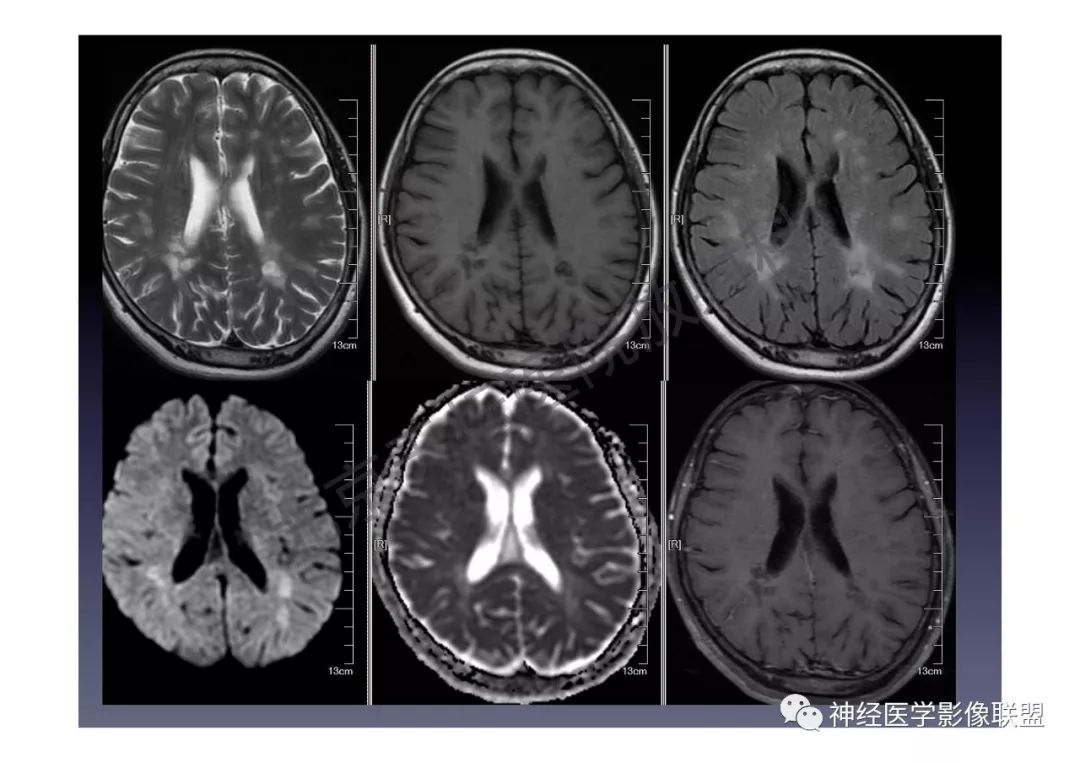

颅内dwi高信号的mri诊断思路